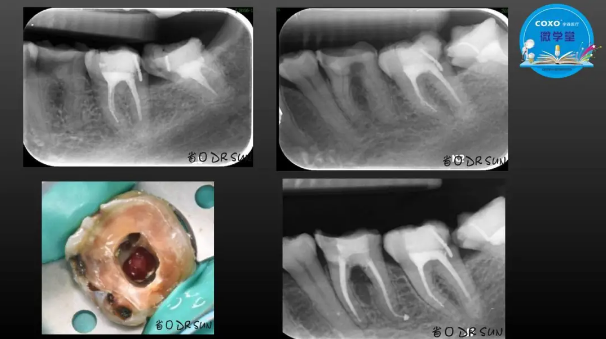

主任醫(yī)師,牙體牙髓副主任, 廣東省口腔醫(yī)院牙體牙髓科 主任醫(yī)師。2003年碩士研究生畢業(yè),研究方向?yàn)檠荔w牙髓病學(xué),擅長(zhǎng)于牙體牙髓病的診斷、齲齒、牙髓炎、根尖周病的治療以及前牙美容修復(fù)。